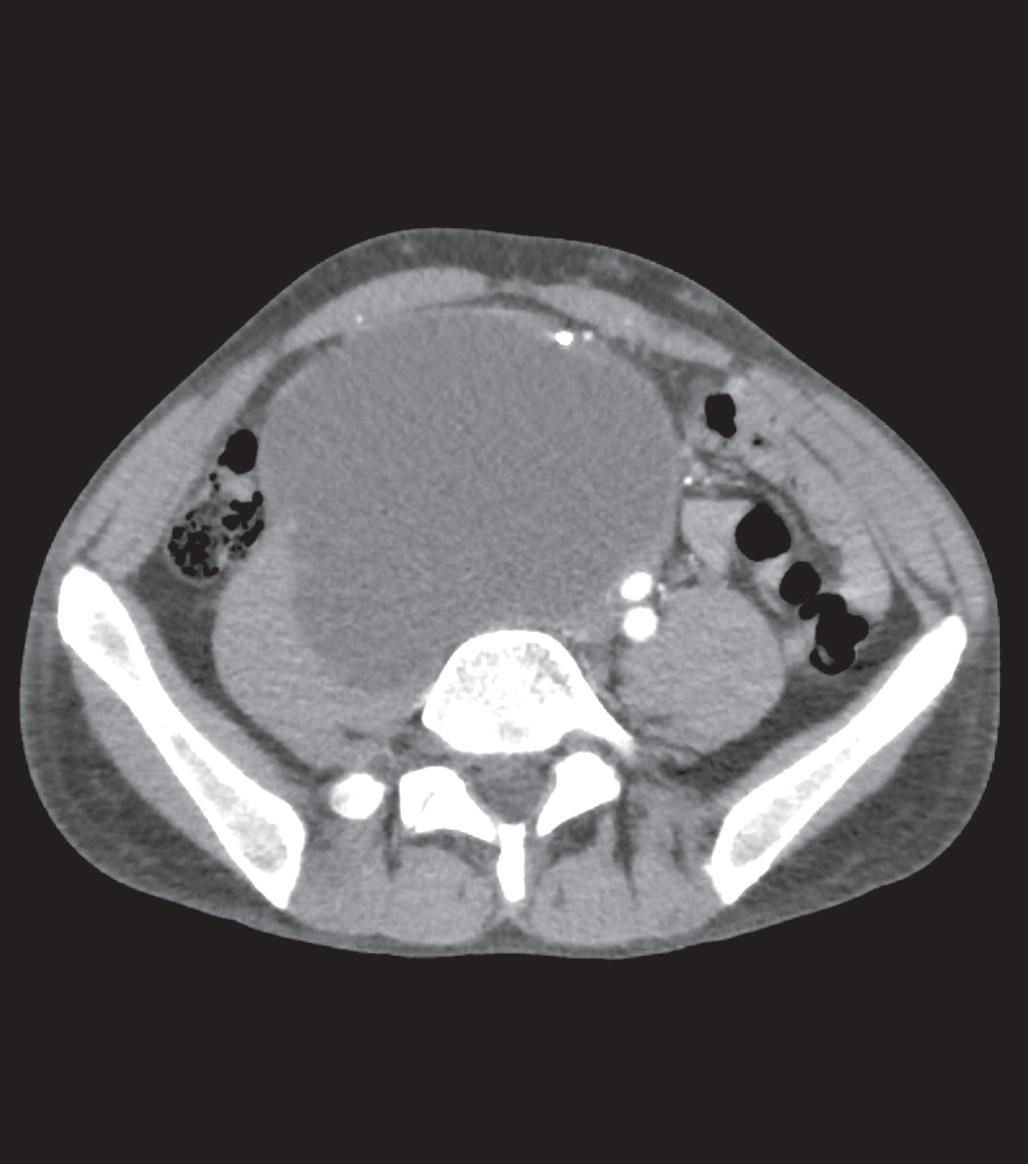

Primární teratom varlete s cystickými metastázemi retroperitonea

Primary testicular teratoma with cystic retroperitoneal metastases

Martin Šabík, Alice Hlobilková, Radek Lakomý, Roman Hrabec, Michal Staník